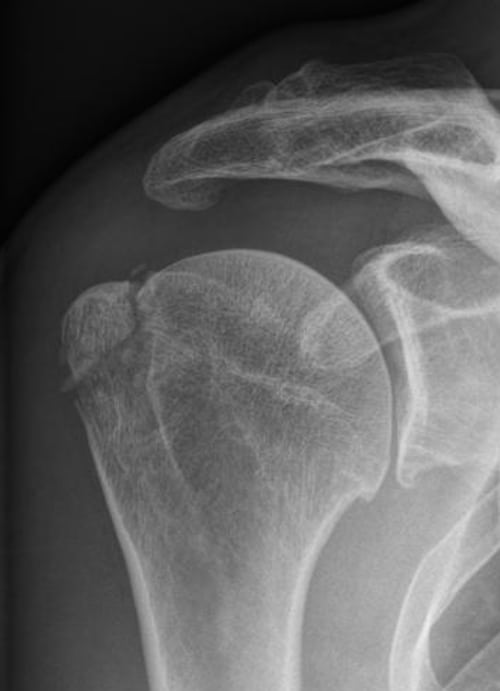

Для подтверждения диагноза проводится рентгенография, а при необходимости — МРТ. Терапия заключается в закрытом или открытом вправлении плечевого сустава, ношении повязки Дезо. На этапе реабилитации пациентам показаны физиопроцедуры, массаж, занятия лечебной физкультурой.

Довольно часто диагностируется сочетание вывиха с травмированием других суставных структур. Это перелом головки, отрыв одного из бугорков кости плеча, перелом впадины сочленения или отростков лопатки (акромиального, клювовидного).

| Формы вывиха плечевого сустава | Характеристика повреждения |

| Передний | Диагностируется в 95% случаев всех вывихов плеча. Плечевая кость смещается кпереди в нижнюю часть клювовидного отростка. Ее головка полностью утрачивает контакт с лопаткой. К вывиху такого вида приводит непрямое травмирование руки, которая в момент повреждения находится в разогнутом положении. Переднее смещение кости провоцирует также прямое механическое воздействие на нее, например, сильный удар сзади |

| Задний | Головка плечевой кости смещается кзади в результате механического воздействия на переднюю область сочленения. В редких случаях задний вывих происходит из-за удара в места, расположенные поблизости плеча — предплечье, локоть, кисть. К заднему смещению костной головки приводит удар в сустав, находящийся в согнутом положении при его вращении |

| Нижний | Самой редкой считается форма вывиха, при которой костная головка смещается вниз относительно лопатки. Сустав травмируется вследствие механического воздействия в положении отведения, например, при поднятии руки вверх. Итогом становится смещение плечевой кости под впадину сочленения с фиксацией конечности в патологической позиции — поднятой над головой. Нередко при нижнем вывихе повреждаются нервы и сосуды, локализованные в подмышечной впадине |